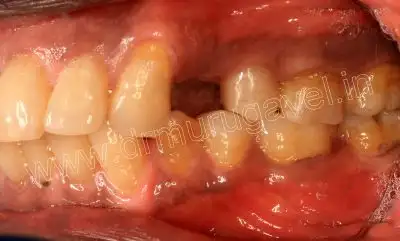

pre-op side view

on examination 14 was missing and grade-2 mobility present in 16..OPG and CBCT taken. CBCT reveals bone loss in relation to 16 region and adequate bone width and height was present in 14 region.